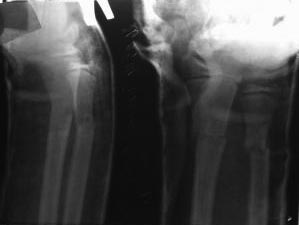

Перелом костей предплечья

В приложении сегодняшний контрольный снимок, 5 день после репозиции. Прошу прощение за неподобающее каяество снимка.

Что скажете?